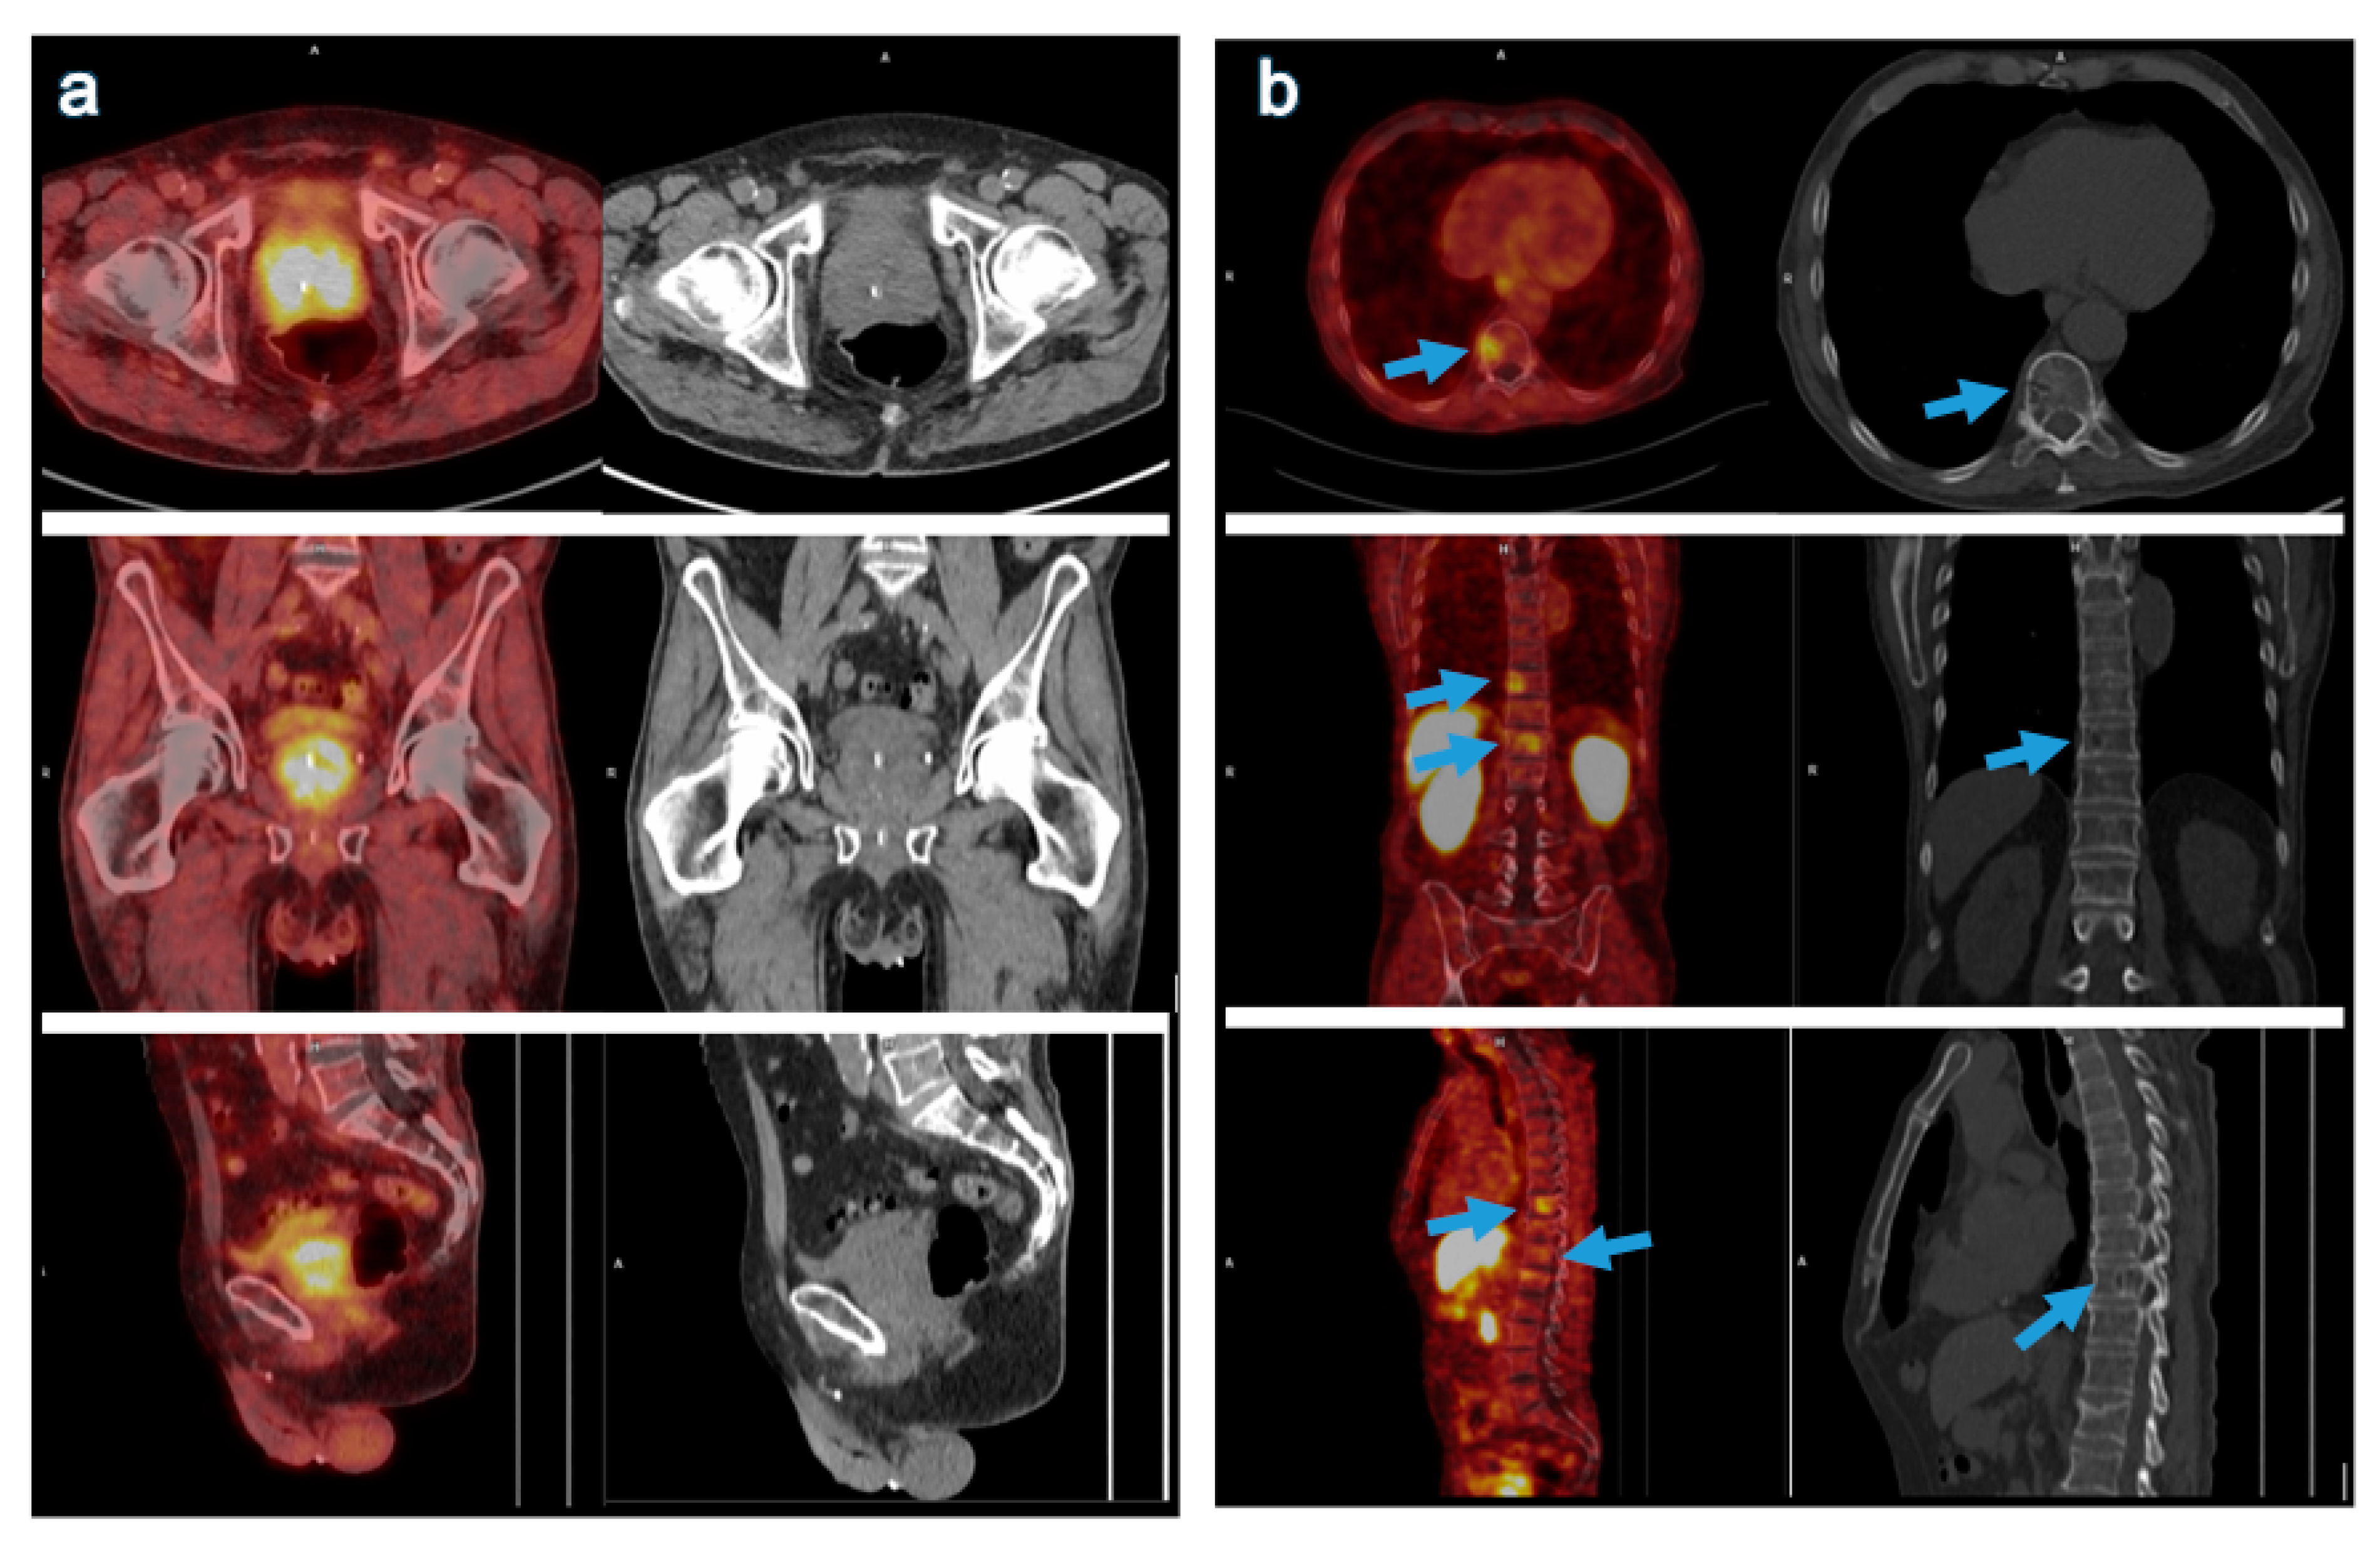

68 Ga Ga Psma 11 A And 18 F Fdg B Pet Ct Images Of A Download Scientific Diagram